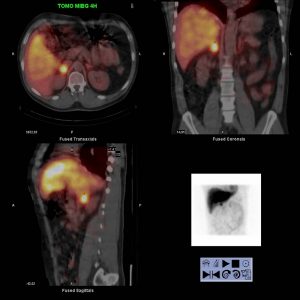

Phéochromocytome droit en SPECT-CT

Recherche de phéochromocytome chez un patient de 37 ans présentant des poussées hypertensives et une élévation des cathécholamines urinairess

Glande surrenale droite de densité tissulaire et présentant un aspect nodulaire (22 X 20 mm) sur les coupes TDM de reperage.

Pas d’anomalies significative sur le balayage corp entier à 4h ou à 24h

Hyperfixation intense et focalisée du radio-traceur en regard de la glande surrenale droite

Pas d’autres foyers hyperfixants ganglionnaires abdomino-pelviens ou viscéral à distance.

Accentuation de la fixation du traceur en regard de la surrénale droite sur les acquisitions à 24H

MIBG-I123

CHU de Montpellier / GE Hawkeye 4

Scintigraphie à la MIBG-I123 en faveur d’un phéochromocytome surrénalien droit isolé. Pas d’autre foyers hyperfixant pathologiques à distance.